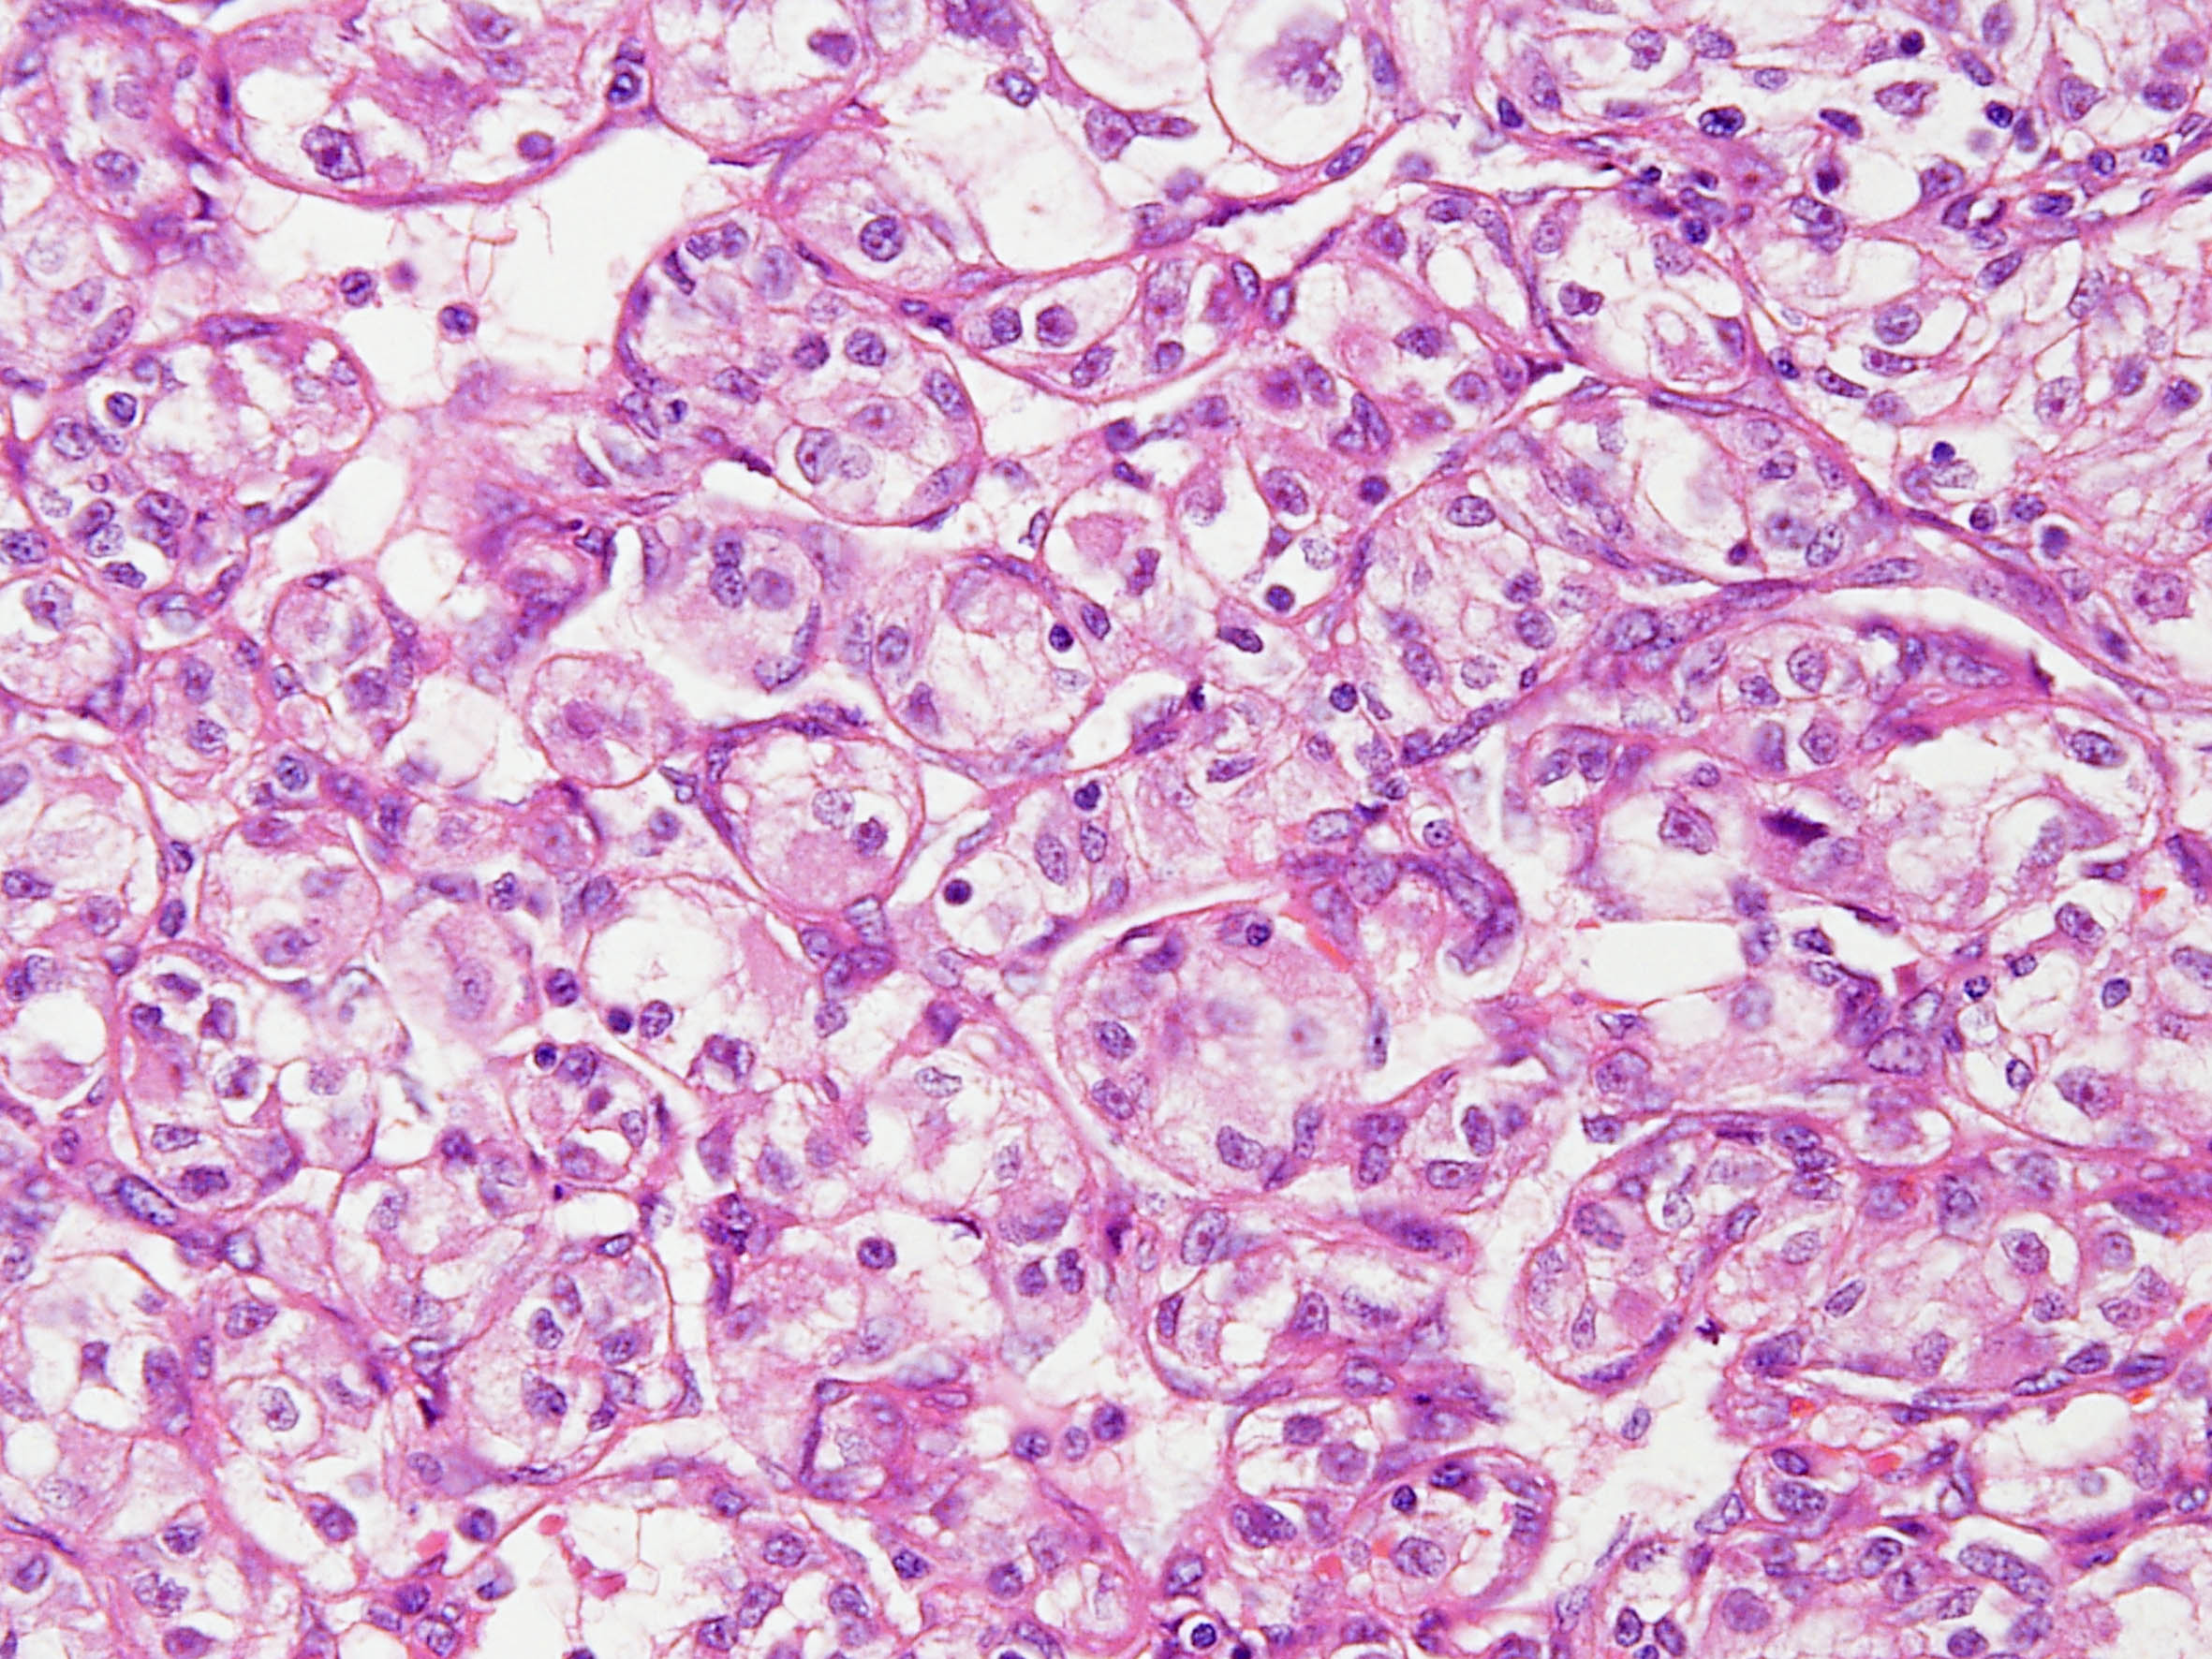

Classification of renal tumors

Case ID: 141